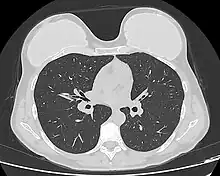

Silicone implant rupture can be evaluated using magnetic resonance imaging; from the long-term MRI data for single-lumen breast implants, the European literature about second generation silicone-gel breast implants (1970s design), reported silent device-rupture rates of 8–15 per cent at 10-years post-implantation (15–30% of the patients).[51][52][53][54]

The study Safety and Effectiveness of Mentor's MemoryGel Implants at 6 Years (2009), which was a branch study of the U.S. FDA's core clinical trials for primary breast augmentation surgery patients, reported low device-rupture rates of 1.1 per cent at 6-years post-implantation.[55] The first series of MRI evaluations of the silicone breast implants with thick filler-gel reported a device-rupture rate of 1 percent, or less, at the median 6-year device-age.[56] Statistically, the manual examination (palpation) of the woman is inadequate for accurately evaluating if a breast implant has ruptured. The study, The Diagnosis of Silicone Breast implant Rupture: Clinical Findings Compared with Findings at Magnetic Resonance Imaging (2005), reported that, in asymptomatic patients, only 30 per cent of the ruptured breast implants are accurately palpated and detected by an experienced plastic surgeon, whereas MRI examinations accurately detected 86 per cent of breast implant ruptures.[57] Therefore, the U.S. FDA recommended scheduled MRI examinations, as silent-rupture screenings, beginning at the 3-year-mark post-implantation, and then every two years, thereafter.[24] Nonetheless, beyond the U.S., the medical establishments of other nations have not endorsed routine MRI screening, and, in its stead, proposed that such a radiologic examination be reserved for two purposes: (i) for the woman with a suspected breast implant rupture; and (ii) for the confirmation of mammographic and ultrasonic studies that indicate the presence of a ruptured breast implant.[58]